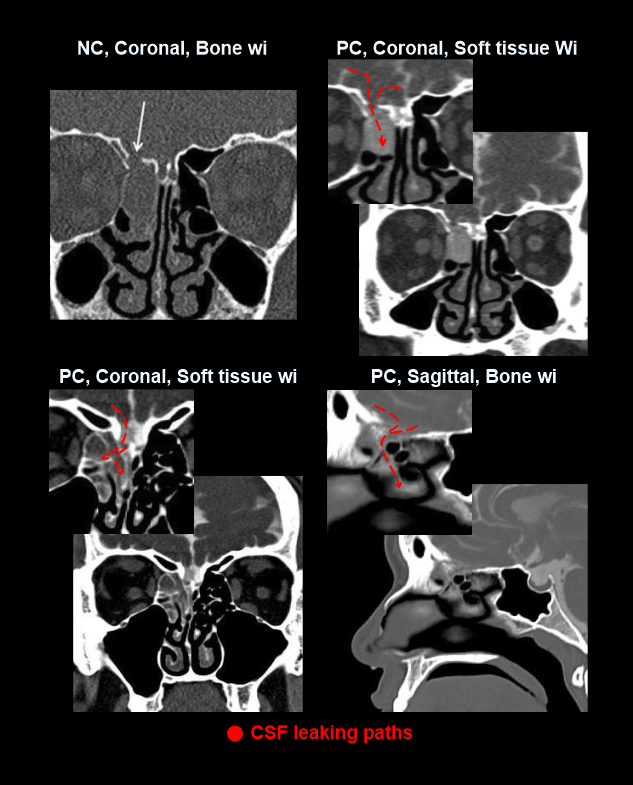

Non-contrast CT head may help to identify contrast leaking areas in comparison with thepost-contrast images.

- Axial, sagittal and coronal images in bone (WW:4500, WL: 450) and soft-tissue (WW:400, WL: 40) windows, with slice thickness lower than 2mm.

Explanation: these images should clearly demonstrate CSF leaks.